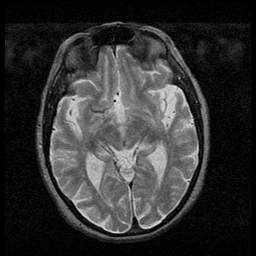

Huntington's Chorea, MR -- Slice #8

[Home][Help][Clinical] Slice 8